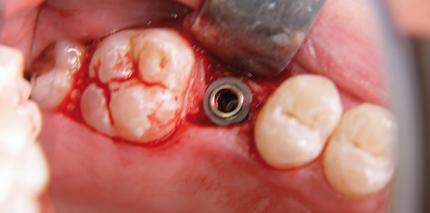

Anhand eines Falles soll dargestellt werden, wie Patienten durch Sorfortimplantation nach Extraktion mit einer festsitzenden Immediatversorgung...

Anhand eines Falles soll dargestellt werden, wie Patienten durch Sorfortimplantation nach Extraktion...